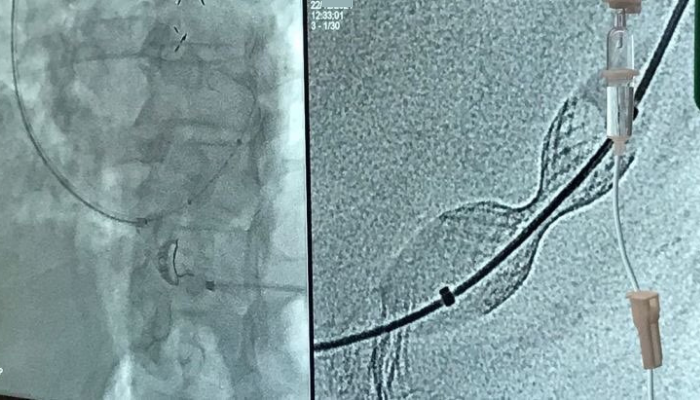

zabieg implantacji reduktora przepływu w zatoce wieńcowej o nazwie REDUCER